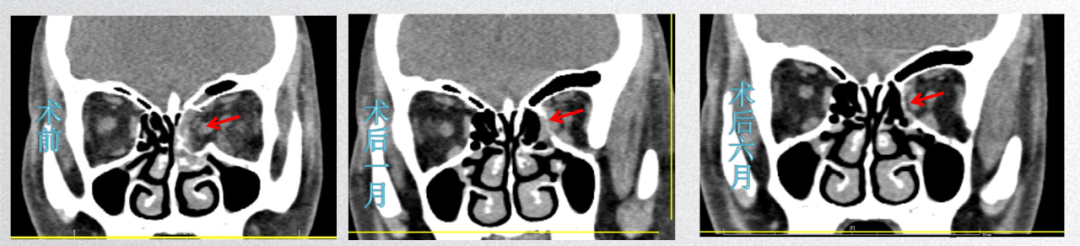

患者女,42岁,左眼被殴打后视物重影伴眼球内陷8天,左眼外转受限(-1)下转受限(-2),眼突度 :13mm>-96mm-<10mm,影像学提示左眼内壁爆裂性眼眶骨折。给予3D打印导航引导内镜联合可吸收植入物手术整复治疗,术后1周,双眼复视消失,左眼外转受限、下转受限恢复,眼突度 :13mm>-96mm-<12mm。

图片

图8.患者术前、术后CT影像学图片